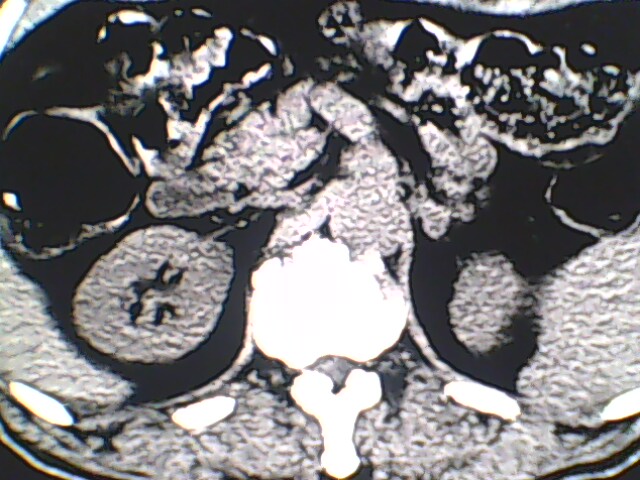

男,56岁,高血压,临床怀疑肾上腺问题,肝脏怎么那么高啊?能描述一下么?

右侧膈膨升,间位结肠,胸腰椎退行性骨关节病,右侧肾上腺可疑增生(图像颗粒太粗,窗太窄,不好看)。

支持 右侧膈膨升,间位结肠;胸腰椎退行性骨关节病;双侧肾上腺可疑增生。